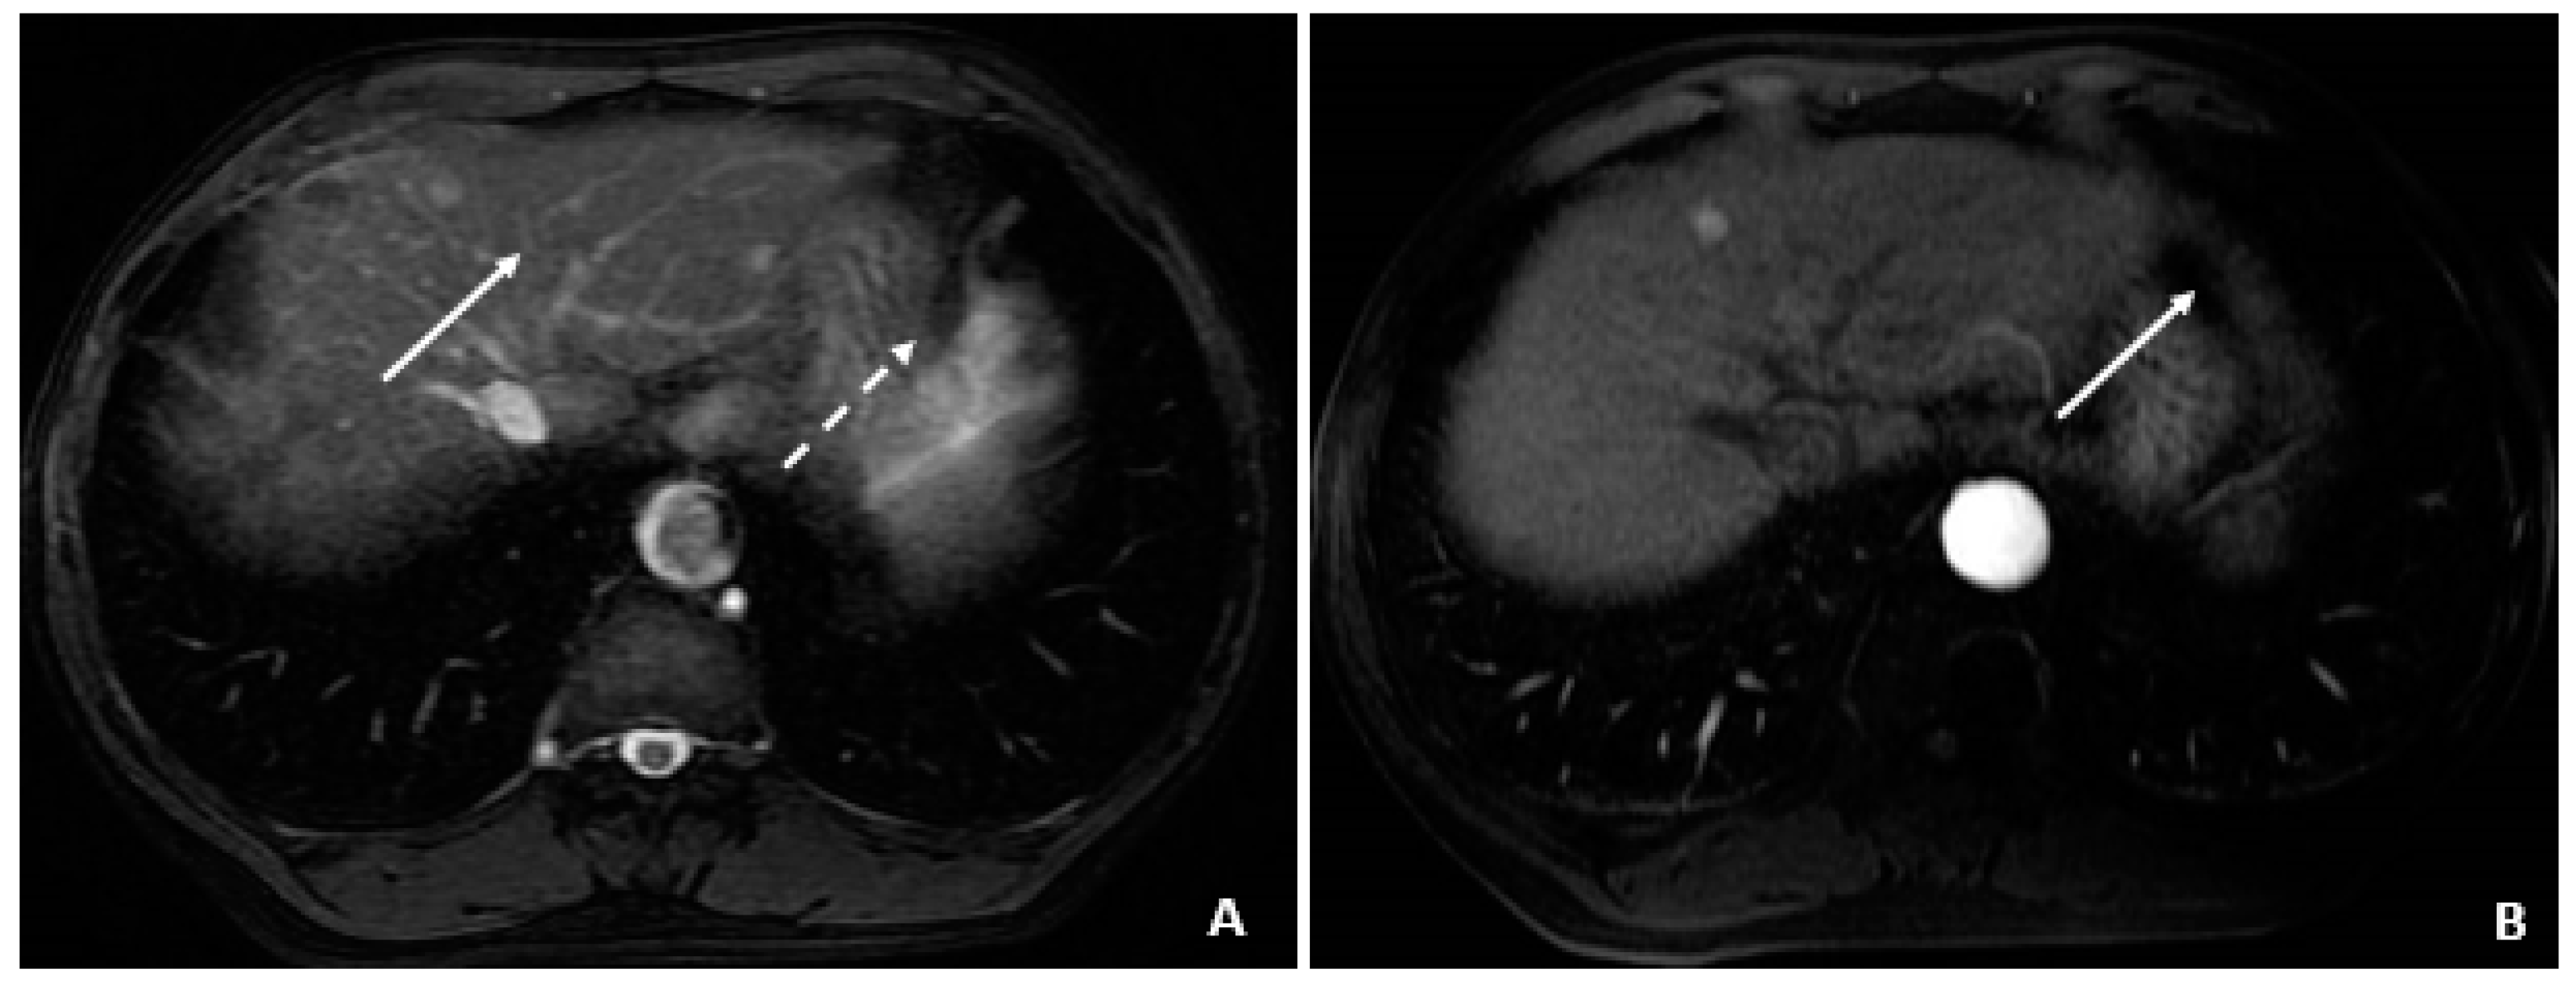

A 58-year-old male was found to have CHB on a routine examination in May 2007. HBV DNA was 4.6 × 105 copies/mL. He was started on telbivudine. The AFP was 3.2 ng/mL in May 2008 with AFP-L3% of 13.8. The MRI in July 2008 showed cirrhosis and no tumor. In August 2008, the AFP remained low at 3.2 ng/mL, but there was a rise in the AFP-L3% to 33.6. The AFP-L3% continued to rise to 69.7 by November 2008, while the absolute AFP value remained at 7.9 ng/mL. In March 2009, the AFP rose to 24.1 ng/mL, and the AFP-L3% at this time was continuing to rise to 87.7. At this time, the abdominal MRI showed a 2.4 × 2.0 cm HCC. He underwent cryoablation followed by radiofrequency tumor ablation and TACE (March and August 2009). These values are outlined in Table 5.

Figure 6.

Cryoablation of the segment 4A HCC (April and May 2009). (A) The CT image through the region of the segment 4A HCC shows the cryoprobes and formation of the surrounding ice ball that accumulates as freezing cycles are applied to ablate the lesion. (B) A delayed postcontrast T1-weighted fat-suppressed image 1 month later shows little to no apparent enhancement in the ablated lesion (arrow).